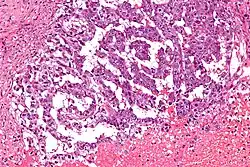

Los tumores vaginales son neoplasias que se encuentran en la vagina. Pueden ser benignos o malignos.[1] Una neoplasia es un crecimiento anormal de tejido que generalmente forma una masa de tejido.[2][3][4] Las neoplasias vaginales pueden ser sólidas, quísticas o de tipo mixto.[5]

Los cánceres vaginales surgen del tejido vaginal, y los sarcomas vaginales se desarrollan a partir de hueso, cartílago, grasa, músculo, vasos sanguíneos u otro tejido conjuntivo o de soporte.[6][7] Los tumores en la vagina también pueden ser metástasis (tejido maligno que se ha diseminado a la vagina desde otras partes del cuerpo).[8][7] El cáncer que se diseminó desde el colon, vejiga y estómago es mucho más común que el cáncer que se origina en la vagina.[9] Algunos tumores benignos pueden progresar hasta convertirse en tumores malignos, como los cánceres vaginales.[10][11] Algunos tumores neoplásicos de la vagina son lo suficientemente raros como para describirse solo en estudios de casos.[3]